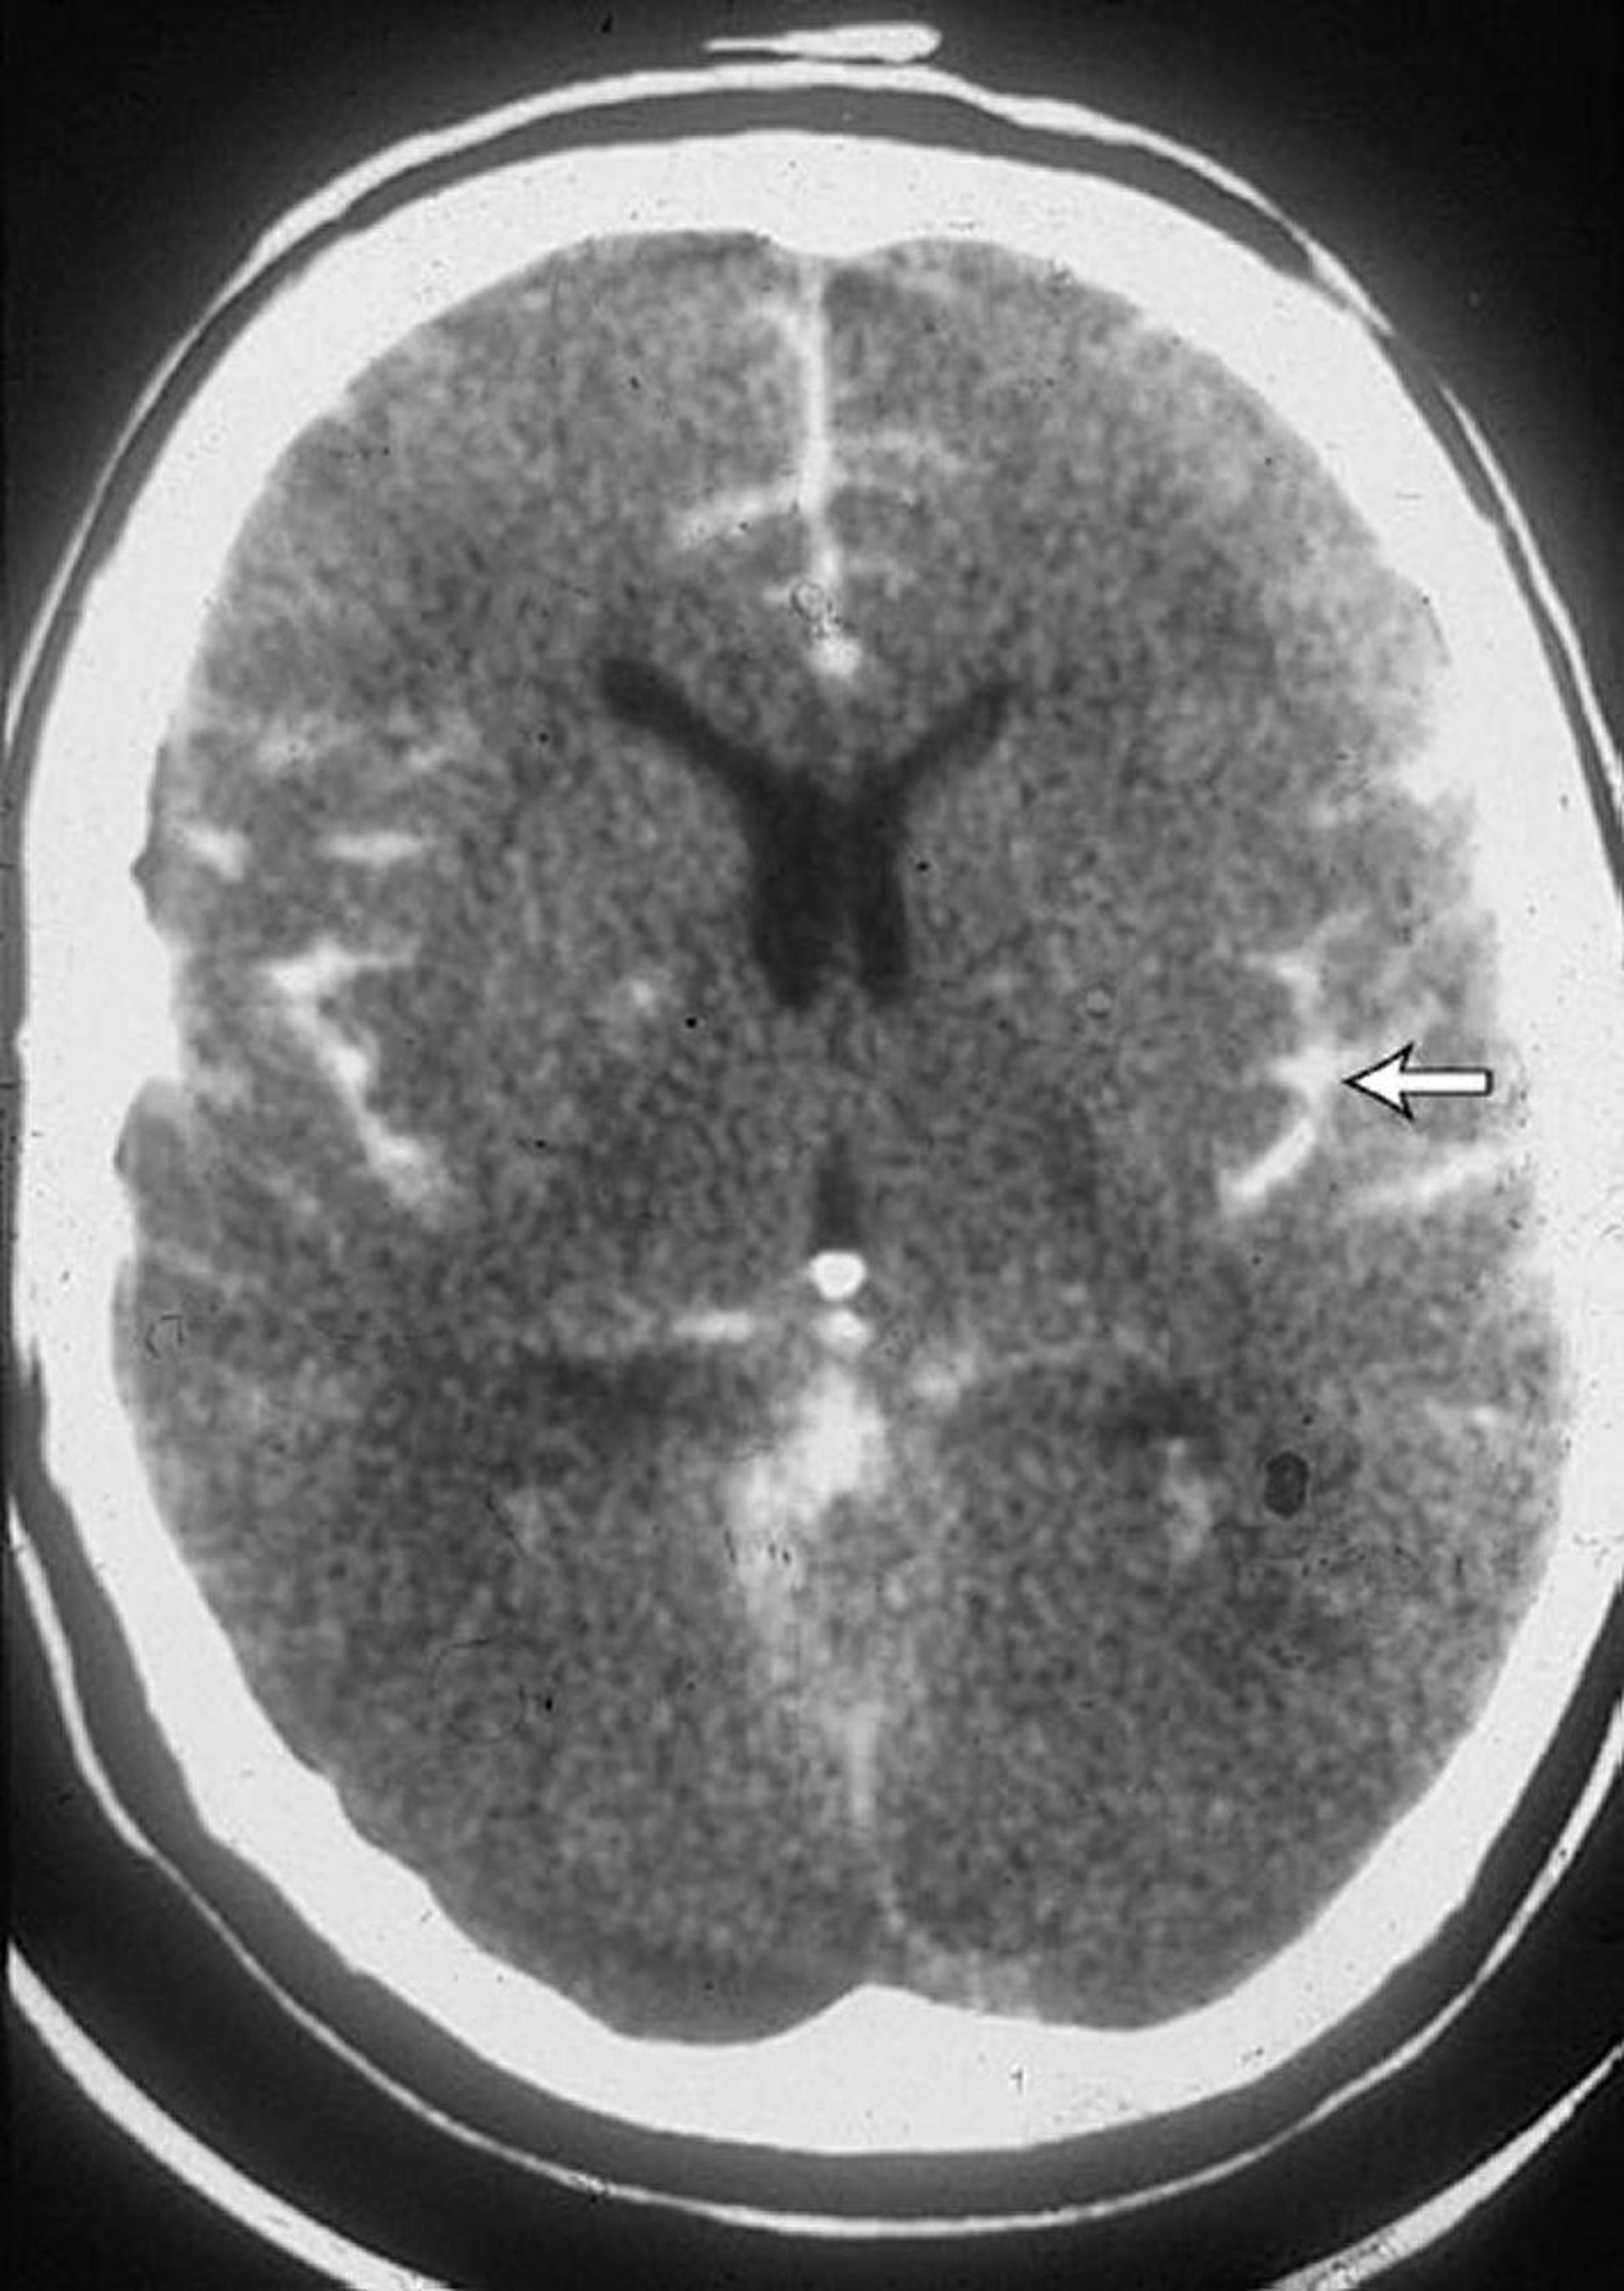

Xuất huyết dưới nhện

CT scan ở một bệnh nhân bị xuất huyết dưới nhện cho thấy máu trong các rãnh cuộn não (mũi tên). Máu cũng thường thấy trong não thất.

Được sự cho phép của nhà xuất bản. Theo Lenaerts M, Couch J. Trong Atlas of Clinical Neurology. Biên tập bởi RN Rosenberg. Philadelphia, Current Medicine, 2002.